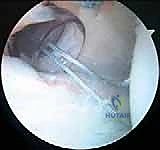

4. تحضير موقع الإصلاح (Preparation):

يتم استخدام أدوات دقيقة لتنظيف الأنسجة التالفة وإزالة أي ندبات. الخطوة الأهم هي "تخشين" (Abrasion) حافة عظم التجويف الحقاني الخلفي. هذا التخشين يهدف إلى إحداث نزيف دقيق يحفز عملية التئام الشفة الممزقة بالعظم لاحقًا.

5. زرع الخطاطيف العظمية (Suture Anchors Insertion):

يتم زرع خطاطيف دقيقة جدًا (غالبًا ما تكون مصنوعة من مواد قابلة للامتصاص الحيوي أو مادة PEEK القوية) في حافة عظم التجويف الحقاني الخلفي. هذه الخطاطيف محملة بخيوط جراحية فائقة القوة.

6. خياطة الشفة وشد المحفظة (Capsulolabral Shift & Repair):

باستخدام أدوات تمرير الخيوط المتطورة، يقوم الدكتور هطيف بتمرير الخيوط عبر المحفظة المفصلية المرتخية والشفة الحقانية المتمزقة. يتم بعد ذلك سحب هذه الأنسجة وربط الخيوط بعقد جراحية محكمة.

هذه الخطوة المزدوجة تحقق هدفين: إعادة تثبيت الشفة في مكانها التشريحي الصحيح (بناء مصد خلفي يمنع خروج العظم)،